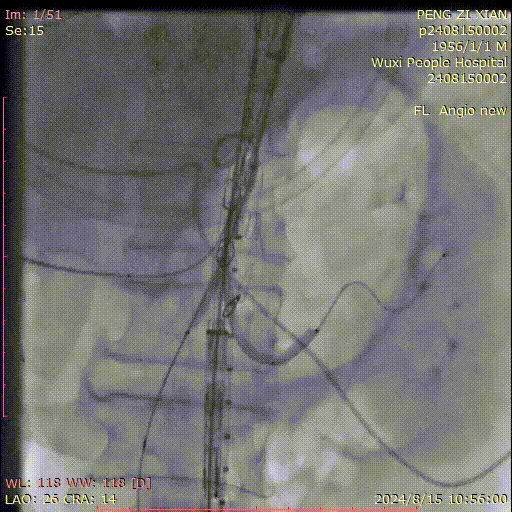

病史:54岁男性,发现胸腹主动脉夹层动脉瘤四天,2011年曾行A型夹层手术史,术后10年未复查。

手术方案:全麻下行胸腹主动脉夹层覆膜支架腔内隔绝,CA、SMA、双侧肾动脉体外开窗重建术。

I期腔内修复过程:

肾动脉至肠上区无破口,病情进展后又进行了二期干预

胸腹主动脉瘤四开窗内脏区重建+远端髂总大破口栓塞

术后效果良好,各分支通畅